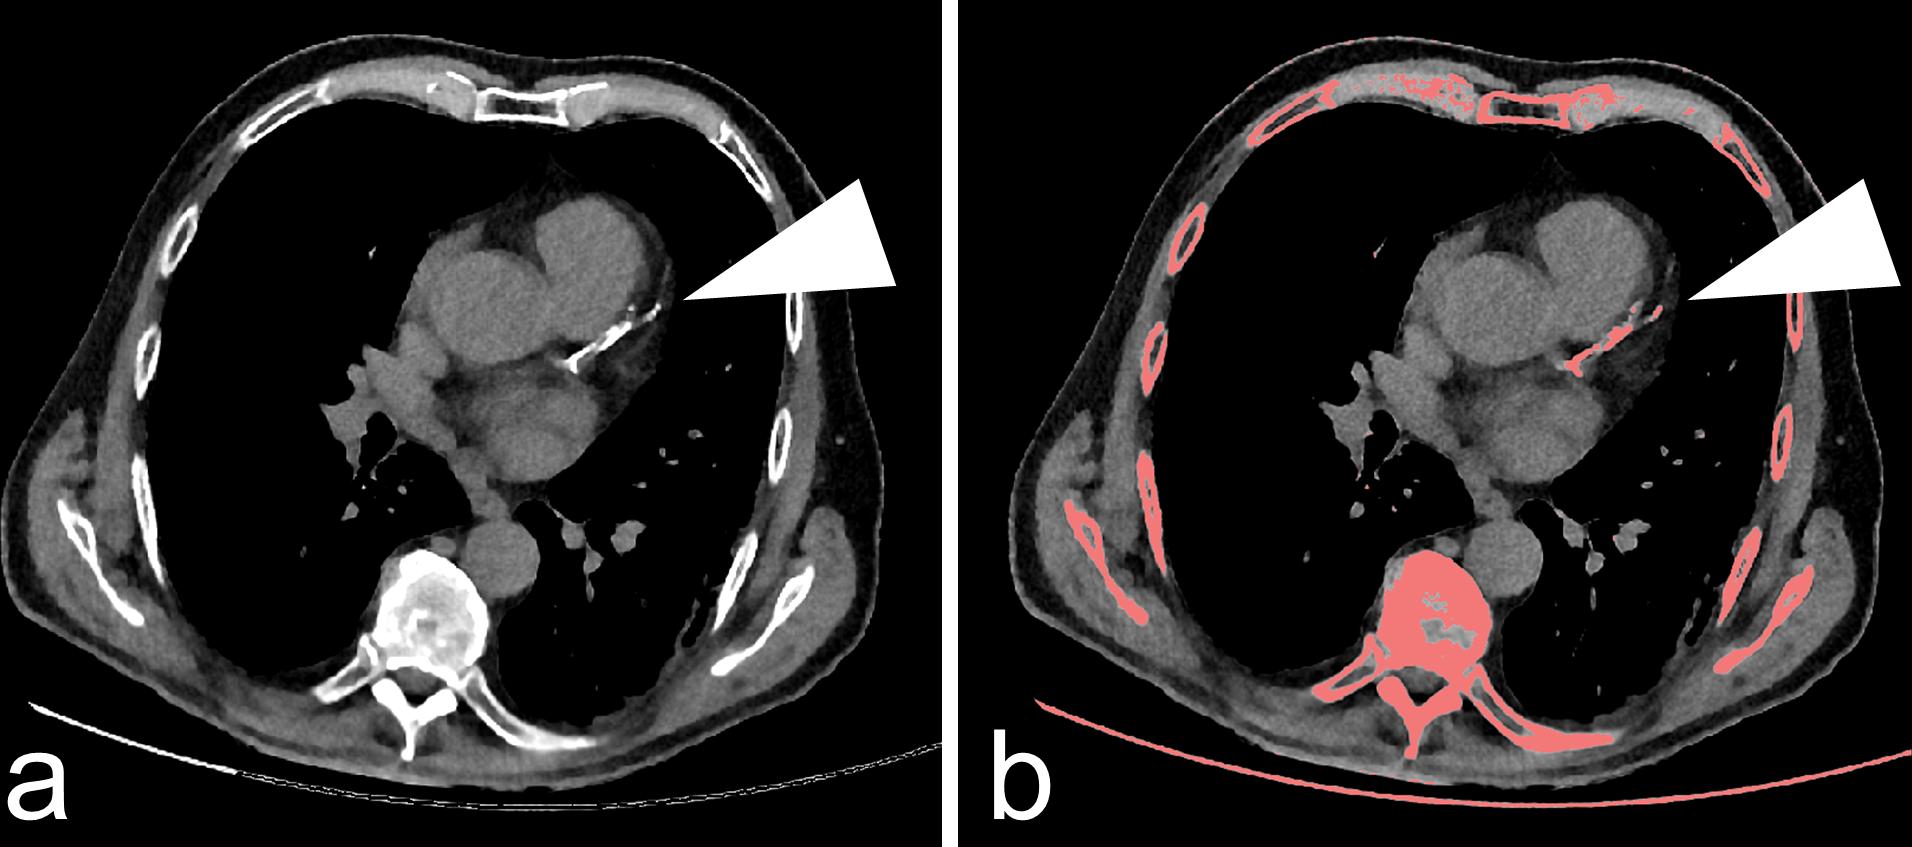

首先,人体内较为粗大的动脉一般都有好几层结构,比如内膜、中膜和外膜。

动脉血管的钙化多出现于内膜和中膜上,但内膜钙化与中膜钙化的意义并不相同。

研究认为,内膜上的钙化往往与动脉粥样硬化显著相关;但中膜上的钙化则更多的与年龄、高血压、慢性肾病等因素有关,与动脉粥样硬化的关联性有限。

而通过CT平扫或X线胸片发现的冠脉钙化,往往难以区分到底是内膜钙化还是中膜钙化。因此,我们还不能把冠脉钙化直接与严重的动脉粥样硬化划等号!